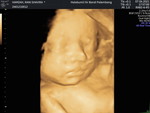

Bun sdh 2bln ini telat haid sampai 1bln lebih, tapi ketika aku slesai berhubungan badan dengan suamiku esoknya langsung haid... Aku jarang brubungan badan karna suamiku kerja di luar kota, jadi kalo dia pulang brubungan badan langsung besoknya... Ada yang sama seperti aku? Kira2 itu knpanya#seriusnanya #bantusharing #pleasehelp #ingintahu #SeriusTanya